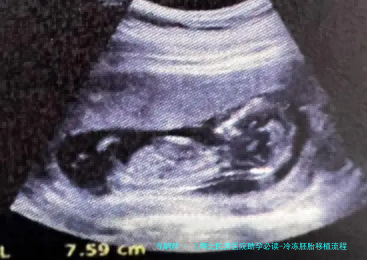

01 冷冻胚胎移植的详细流程

冷冻胚胎移植是一项邃密化的生殖诊疗技术,整个过程须要医生准确把握移植时机。其核心在于保证胚胎形成与子宫内膜发育的同步进程,为胚胎着床创造最完美条件。

在移植当日,实践室医生会将挑选的冷冻胚胎冻结,并评估其存活情况和质量。随之在B超引导下,医生使用一根细软管将胚胎精准放置到子宫腔内最完美位置。移植后,病人须要遵医嘱使用黄体支持药物,直至移植后十日至十四日进行验孕。